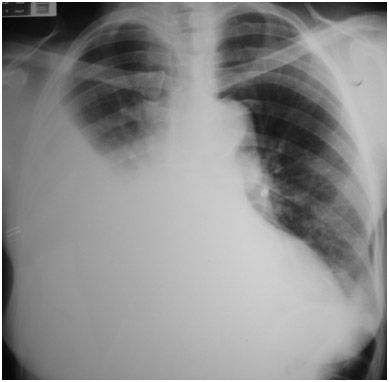

2. Imagenología

1. Desplazamiento hacia afuera del vértice del diafragma

1. con una pendiente súbita hacia el surco CF

1. Separación > 2cm entre la búrbuja de aire gástrica y pulmón

2. RX

1. Lateral

1. 75-100 mL acúmulo en surco costofrénico- POST-> visible

2. PA

1. 175-200 ml surco CF Lateral --> deliniarse imagen frontal